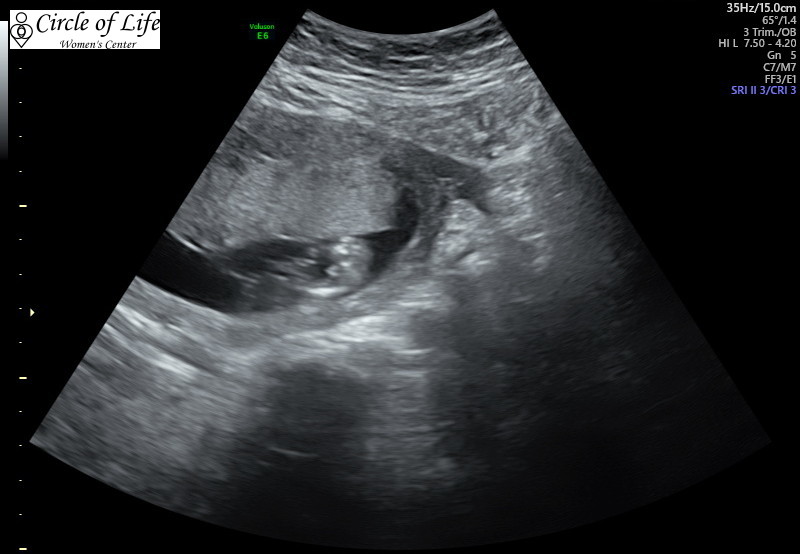

Saw my doctor for a follow-up appointment and confirmed a baby boy! That makes two girls and two boys!

Attachment 42128